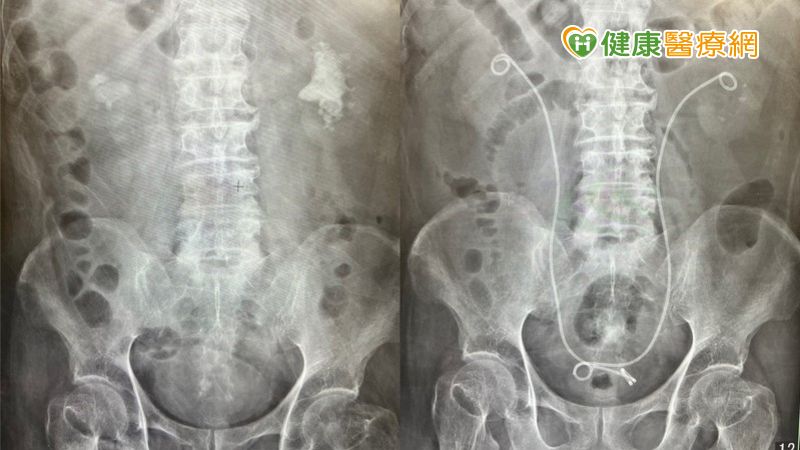

南投一名65歲男性長期有腎結石狀況,也曾在外院接受體外震波治療,依舊無法將石頭排乾淨。由於疫情中斷定期檢查,血尿狀況頻繁發生後,就醫才發現結石已有8公分之大,為了降低對腎臟傷害及手術併發症,後續病人接受「新式Mini軟式輸尿管鏡內視鏡手術 (Mini RIRS)」治療,即便是8公分巨無霸的腎結石也一次吸除乾淨,並且沒有任何傷口。

新式Mini軟式管徑7.5Fr相較於一般軟鏡管徑9Fr大幅減少30%,降低輸尿管損傷率,且有效降低手術併發症及提升成功率。新式Mini軟式輸尿管鏡內視鏡手術,又稱為吸石雙嬌,「管徑7.5Fr Mini軟式輸尿管鏡搭配可彎曲專利吸引導管」有別於以往軟式輸尿管鏡手術,無須使用取石網取石,邊打邊吸,縮短手術時間,提升清石效率!

● 新式Mini軟式輸尿管鏡內視鏡手術 (Mini RIRS):又稱為吸石雙嬌,管徑7.5Fr Mini軟式輸尿管鏡&可彎曲專利吸引導管,擊碎結石效果佳,跟一般軟鏡相比,直徑大幅小於30%,可以穿梭在較細的腎盞及漏斗之間,邊打結石邊吸石,無需使用取石網取石,病患也無須擔心石頭是否有完全排出,目前仍屬於自費手術,健保並未納入給付。